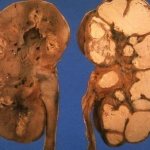

Несмотря на сравнительную легкость визуального осмотра полости мочевого пузыря с помощью цистоскопа, своевременная и правильная диагностика рака мочевого пузыря не всегда возможна из-за стриктуры уретры, больших размеров аденомы предстательной железы, малой емкости мочевого пузыря, внутрипузырных изменений слизистой оболочки, которые встречаются у 6 — 20% больных [Петрова А. С. и соавт., 1981].

В таких случаях цитологическое исследование является одним из методов, с помощью которых можно обнаружить злокачественный процесс в органах мочевой системы.

Цитологическую диагностику опухолей мочевого пузыря начали применять еще во II половине XIX века, но наибольшее распространение она получила после описания общих принципов получения, окраски и микроскопического исследования нативных [Альтгаузен А. Я., 1948] и окрашенных препаратов. Эти методики в основном связаны с изучением осадка свежевыпущенной мочи.

Цитологическая картина зависит от клинико-анатомической формы и гистологического строения опухоли и характеризуется следующими основными признаками:

1. полиморфизмом клеток;

2. нарушением ядерно-цитоплазменного соотношения в сторону увеличения ядра;

3. увеличение количества ядрышек;

4. изменением структуры хроматина.